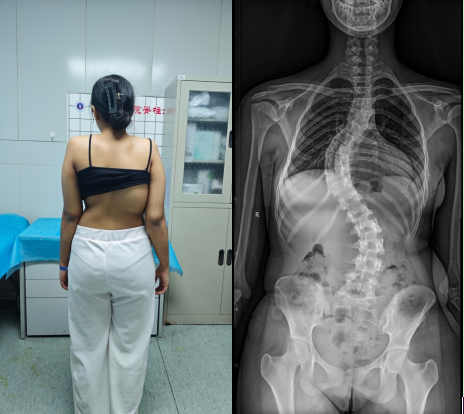

患者入院后,科室立即启动针对外籍患者的规范化诊疗流程,在语言沟通、检查安排、病情评估及围术期管理等方面进行系统协调。影像学检查显示,患者胸椎主弯 Cobb 角快70°,伴明显椎体旋转,属于重度脊柱侧弯。该类患者手术涉及多节段矫形、脊髓安全保护及整体力学重建,对团队经验与协作能力要求极高。在骨科中心李浩鹏主任以及脊柱与骨肿瘤病区王栋主任、蔡璇副主任的统筹下,医院组织脊柱外科、麻醉科、影像科、神经电生理监测及护理团队开展多学科会诊(MDT),围绕手术策略、神经安全、失血控制及术后康复等关键环节,为外籍患者制定个体化治疗方案。与此同时,为保障患者顺利完成治疗,护士长李珂、陈静提前部署护理方案,安排专人全程负责护理工作,并指派英语沟通顺畅的陪护人员协助患者完成各项检查及术后护理,有效解决了语言与文化差异带来的就医障碍。

手术由脊柱与骨肿瘤病区副主任蔡璇教授主刀,李宇欢、王杰主治医师及刘璇规培医师协助,在全麻下实施后路多节段截骨矫形、植骨融合及内固定术。手术过程中需在大幅度矫正畸形的同时,严格防控脊髓神经损伤风险。神经电生理监测团队黄亚娟、孙丽君医师全程实时监测神经传导功能,为手术安全提供关键保障。在麻醉医师李路盼和手术室彭维、张宇坤主管护师的熟练配合下,历时6小时,手术顺利完成,术中出血量约600 ml,未发生神经损伤等严重并发症。术后影像学评估显示,胸椎主弯矫形率超过90%,脊柱整体序列显著改善。术后,患者在多学科团队的协同管理下恢复良好,双下肢感觉及运动功能正常,身高增加7 cm 以上。护理团队结合外籍患者需求,提供细致的围术期护理与康复指导,帮助患者顺利过渡至日常生活与学习状态。出院前,患者用英语向医护人员表达感谢:“Thank you for giving me a new life。”这不仅是对治疗效果的肯定,也体现了患者及家属对中国医疗技术与服务体系的高度认可。